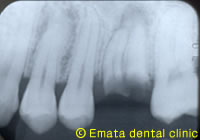

患者さんは栃木県の東方から当院のホームページをみて来院しました。カリエスが大きく「抜歯をしない治療法」で治療できないかとうことでした。残念ですが適応症ではありません。右上の奥歯に使ってない親知らずがあります。

抜歯後の治療法として、入れ歯・ブリッジ・インプラント・歯牙移植の治療法その長所・欠点を説明しました。患者さんは「隣の健康な歯は絶対削りたくない」とういことで、迷わずインプラントでなく歯牙移植の治療を選択しました。皆さん、人工臓器より天然臓器の移植が一番いい治療だとお分かりになっているようですね。

使ってない3本の親知らずがありました。 |